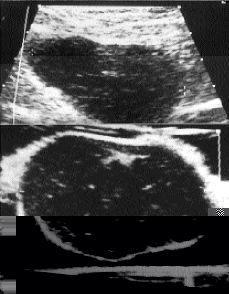

En todos los casos, excepto el número 1, tanto la mamografía (Fig. 3) como la ecografía detectaron la presencia de los ganglios intramamarios. Todos ellos se presentaron como nódulos bien circunscritos. En la ecografía practicada in vitro en el ganglio del caso 4 se apreciaron las características propias de las adenopatías metastásicas como son una morfología esférica y ausencia de la región hiliar (Fig. 4).

Fig. 4. A: Ecografía del ganglio linfático intramamario metastásico demostrando una homogenicidad en su ecoestructura. B: Ecografía in vitro del mismo ganglio donde se observa una forma esférica y ausencia de la zona hiliar (caso 4).